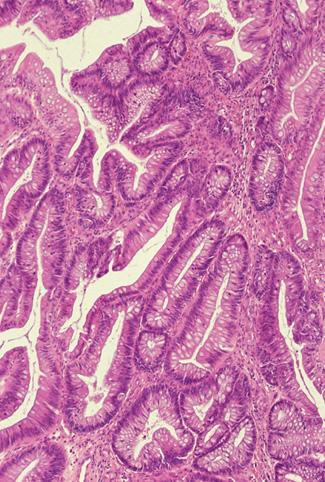

A case of adenoma occurring in the inverted appendix which intussuscepted into the ascending colon.

[ Image ID:9519 ]

Criteria of Hist.Classification

Tumor-like lesions/Others

Location

Large intestine(Colon)/Appendix

Technique, Method

Histology

Size

40 -